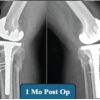

A 77-year-old male with right knee pain was diagnosed with advanced OA. In pursuit of relief, the patient underwent GAE at another hospital. Following the procedure, the patient developed swelling, increased pain, and skin discoloration, necessitating readmission to the same hospital for vascular observation and pain control. Redness, swelling, and pain subsided over a period of 7 days, and the patient was discharged from the hospital (Fig. 1). After a 6-month recovery period, owing to persistent osteoarthritic knee pain, the patient sought further treatment options at our hospital. Upon consultation with our radiologists, an arteriogram was performed 1 year after embolization, and it was ascertained that the genicular arteries remained patent (Fig. 2). Consequently, a decision was made to proceed with total knee arthroplasty to manage OA. During arthroplasty, bone samples of bone cuts from the weight-bearing distal femur and proximal tibia were sent for histopathological examination, and the results were negative for osteonecrosis (Fig. 3). The post-operative period involved meticulous monitoring of complications such as wound dehiscence, tissue necrosis, and infection. Fortunately, aside from the mild erythema observed around the knee a week after the procedure, which did not require any treatment, the wound healed well without any complications, with standard rehabilitation of same-day walking, and ROM exercise could be initiated (Fig. 4 and 5). After 1 year of follow-up, the patient experienced relief of knee pain and achieved a knee range of motion of up to 0°–120° and back to his day-to-day activities, indicating a successful outcome following total knee arthroplasty (Fig. 6 and 7).